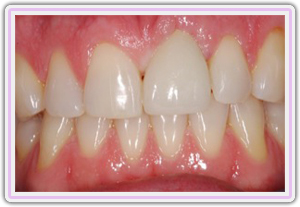

One Year Post Op Healing Picture

Procera Full Porcelain Crown In The Implant

Six Months Post Op Healing Picture